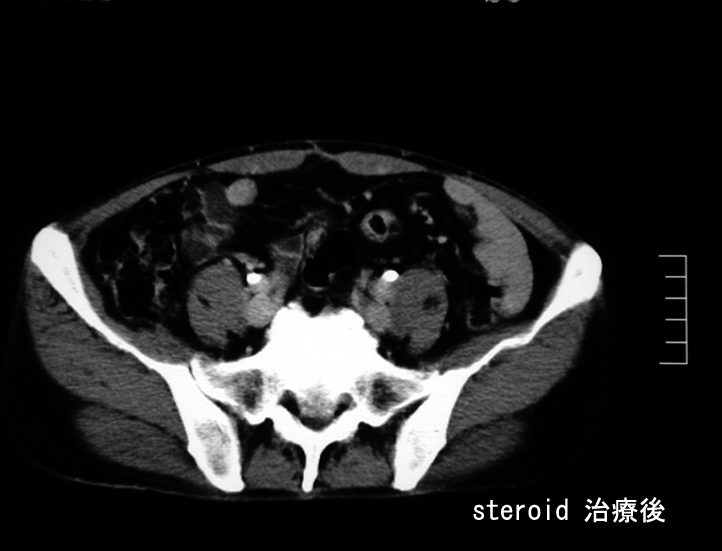

悪性リンパ腫や膵癌など悪性腫瘍は否定され自己免疫性膵炎と診断し, steroid治療を開始する。約2ヶ月の投与で, 膵、腹腔腫瘤は著明に縮小または消失しました。steroid減量中に黄疸が出現, 画像診断で硬化性胆管炎の合併をうたがいsteroidを増量、黄疸は消失。以後steroid をゆるやかに漸減し中止したが症状の再発はない。

pancchiryogo.jpg

abdtumorgo.jpg

Steroid 治療2ヶ月後のCT; 腫瘤性病変の著明な縮小と消失が確認できる。